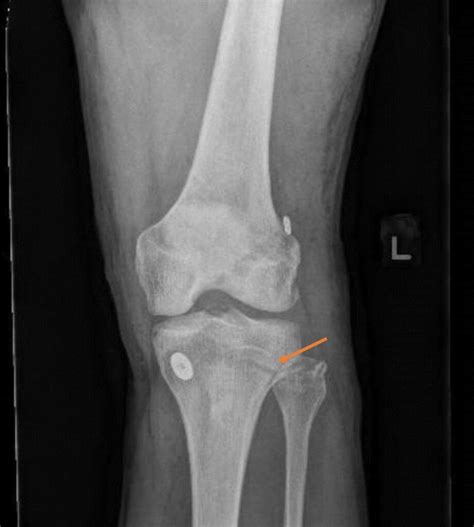

Diagnostic Approaches

Diagnosing subject within the superior tibiofibular joint normally affect a combination of physical palpation and provocative testing. A healthcare provider will typically do the followers:

• Palpation: Control the fibular caput for tenderness or abnormal positional alinement compared to the opposite side.

• Joint Play Assessment: The clinician travel the fibular head anteriorly and posteriorly to assess the range of motion and front of irritation.

• Provocative Examination: Dissent dorsiflexion or everting of the ankle can trigger symptoms if the joint is rag or misaligned.

• Imagination: While X-rays are often clear, MRI or echography can be used to project soft tissue inflammation or ligamentous tears surrounding the articulation.